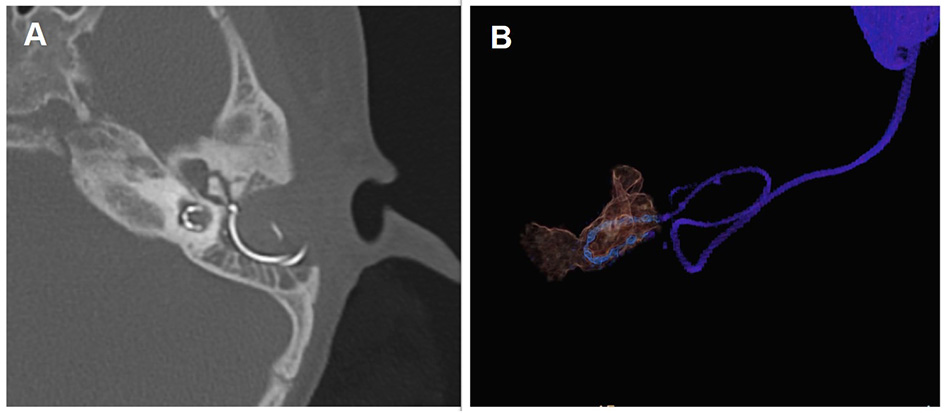

All the participants underwent a routine otorhinolaryngological examination, followed by audiological evaluation and preoperative CT and MRI scans. The patients underwent CI with customized electrodes (MED-EL Medical Electronics, Innsbruck, Austria) by means of the transmastoid slotted labyrinthotomy approach (TSLA), in accordance with the technique described in previous literature (4). A curved labyrinthotomy was performed and the electrode was positioned within the cavity and filled with muscle. The electrode placed within the common cavity is shown in Figure 1. None of the patients displayed any postoperative complications such as facial paralysis or cerebrospinal fluid leakage.

Figure 1

Post-operative computed tomography (CT) scan showing electrodes in CCD patients. (A) CT scan of the temporal bone with electrode in the axial position; (B) Three-dimensional reconstruction of the electrode and common cavity.